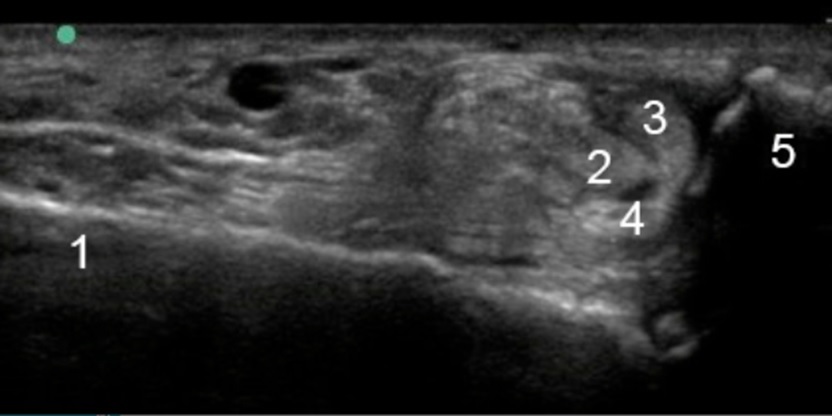

Bild: Fuß und Sprunggelenk, laterale Sehnenruptur, Peronealsehne

1. Calcaneus

2. Peroneus longus

3. Peroneus brevis

4. Peroneus brevis

5. Malleolus lateralis